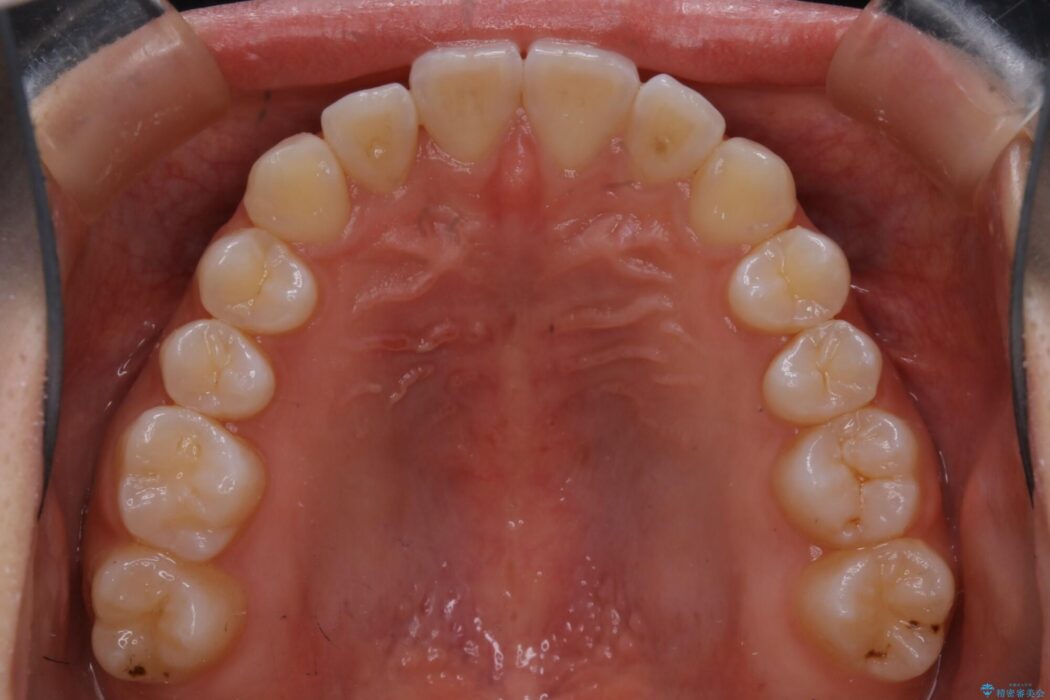

治療後について

正常な噛み合わせ位置へと改善したことにより奥歯で噛みしめることができ、加えて見た目も受け口から変わって大変ご満足いただけました。